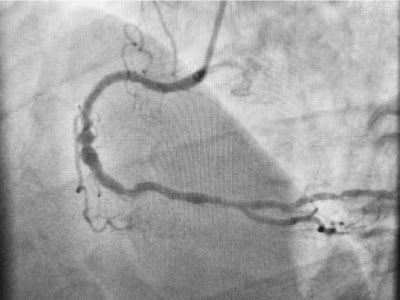

В 03:30, примерно через 11 часов после обращения, пациента доставили в рентгеноперационную:

99% окклюзия проксимального сегмента ПКА с потоком TIMI 2. На этом снимке с экрана видно небольшое количество контраста, затемняющего сосуд, дистальный от поражения.

После установки стента:

Сосуд теперь открыт с потоком TIMI 3, хотя он диффузно поражен, а средний сегмент расширен.